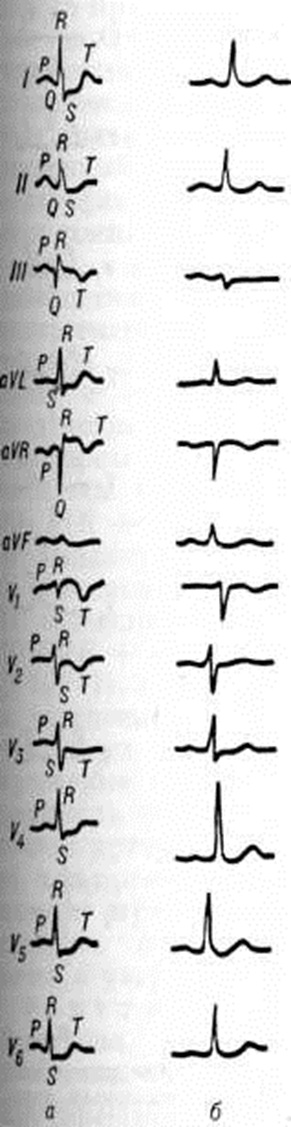

Клинические проявления и течение. Острое Лёгочное сердце при тромбоэмболии лёгочных артерий проявляется быстро прогрессирующей недостаточностью правого желудочка на фоне явной лёгочной артериальной гипертензии. Характерны выраженная одышка, диффузный цианоз, набухание шейных вен, видимая пульсация грудной стенки и (или) подложечной области. Глубокая пальпация под мечевидным отростком выявляет нередко упругий напряжённый толчок правого желудочка сердца. При перкуссии выявляется расширение границ относительной сердечной тупости вправо. Характерна тахикардия с числом сердечных сокращений более 100 в 1 минуту. Нередко определяется маятникообразный ритм звучания сердечных тонов. Второй тон сердца усилен, отмечается резкий его акцент над лёгочной артерией. артериальное давление, как правило, снижено, возможен коллапс. Печень часто выступает из-под рёберной дуги, край её нередко болезнен; иногда жалоба на боль в правом подреберье (в связи с острым растяжением капсулы печени) становится одной из доминирующих; возможны тошнота и рвота. На ЭКГ определяются признаки перегрузки правого предсердия (высокие заострённые — «лёгочные» зубцы Р во II и III стандартных отведениях, преобладание положительной фазы зубца Р в отведении V1) и правого желудочка, что проявляется отклонением электрической оси сердца вправо (более заметным при сравнении с ЭКГ, зарегистрированными до заболевания), появлением или увеличением зубцов R или R в однополюсных отведениях от правой руки и правых грудных, углублением зубцов S в левых грудных отведениях и смещением вниз сегмента S — Т в отведениях II, III, aVP. Изменения ЭКГ при остром Лёгочное сердце вследствие тромбоэмболии лёгочной артерии (в частности, синдром SIQIII) могут имитировать картину инфаркта миокарда задней стенки левого желудочка (рисунок 2).

Начальные изменения ЭКГ при хронический заболеваниях лёгких чаще всего отражают ротационные сдвиги: 1) вертикальная или полувертикальная позиция сердца (в ряде случаев с отклонением электрической оси сердца вправо); 2) сдвиг переходной зоны влево за счёт поворота сердца по часовой стрелке вокруг продольной оси; 3) отклонение верхушки назад в связи с поворотом вокруг поперечной оси сердца. Диффузные изменения миокарда проявляются прежде всего уменьшением амплитуды зубцов комплекса QRS. Прогрессирование лёгочной артериальной гипертензии отражается на ЭКГ изменением предсердного компонента по типу «лёгочного» зубца Р (pulmonale). При различных формах гипертрофии правого желудочка встречаются разные типы кривых ЭКГ; в зависимости от преобладания зубца R в правых грудных отведениях или зубца S в левых грудных говорят о R-типе или S-типе, а при комбинации этих признаков — о Rv1— Sv5-типах кривой (рисунок 3). Для R-типа кривой ЭКГ характерен зубец Rv1 без выраженного зубца Sv5 (результирующий вектор отклоняется при этом вправо и вперёд), для S-типа — малый зубец Rv1 и глубокий зубец Sv5 (результирующий вектор отклоняется вправо и назад). Промежуточные формы кривой ЭКГ с несколько увеличенным зубцом Rv1 и довольно выраженным зубцом Sv5 дают отклонение результирующего вектора только вправо.

Электрокардиографической диагностике Лёгочное сердце способствует тщательная оценка прямых и косвенных (обусловленных преимущественно позиционными изменениями сердца) признаков гипертрофии правого желудочка. Выделяют следующие прямые признаки гипертрофии правого желудочка: ![]() 3) Rv1 + Sv5 ≥ 10,5 миллиметров; 4) время внутреннего отклонения в отведении V1 — 0,03—0,05 секунд; 5) форма QRv1; 6) Rv1 > 10 миллиметров при неполной блокаде правой ножки; 7) Rv1 > 15 миллиметров при полной блокаде правой ножки; 8) признаки систолической перегрузки правого желудочка в отведениях V1,2. Наряду с этим различают 12 косвенных признаков гипертрофии правого желудочка:

3) Rv1 + Sv5 ≥ 10,5 миллиметров; 4) время внутреннего отклонения в отведении V1 — 0,03—0,05 секунд; 5) форма QRv1; 6) Rv1 > 10 миллиметров при неполной блокаде правой ножки; 7) Rv1 > 15 миллиметров при полной блокаде правой ножки; 8) признаки систолической перегрузки правого желудочка в отведениях V1,2. Наряду с этим различают 12 косвенных признаков гипертрофии правого желудочка: ![]() ; Rv1 миллиметров при неполной блокаде правой ножки; 5) Rv1 < 15 миллиметров при полной блокаде правой ножки; 6) индекс

; Rv1 миллиметров при неполной блокаде правой ножки; 5) Rv1 < 15 миллиметров при полной блокаде правой ножки; 6) индекс ![]() - 7) отрицательные зубцы Tv1-3; 8) < 2 миллиметров; 9) Р pulmonale (высокие, часто остроконечной формы зубцы) во II и III отведениях; 10) электрическая ось ЭКГ по стандартным отведениям > 110°; 11) тип ЭКГ SI — SIII; 12) R/QaVR > 1. Сочетание двух или более прямых признаков делает диагноз гипертрофии правого желудочка несомненным. При наличии одного прямого и одного косвенного или двух непрямых признаков гипертрофия правого желудочка представляется вероятной. Если же имеется только один прямой или один косвенный признак, то диагноз гипертрофии правого желудочка остаётся сомнительным.

- 7) отрицательные зубцы Tv1-3; 8) < 2 миллиметров; 9) Р pulmonale (высокие, часто остроконечной формы зубцы) во II и III отведениях; 10) электрическая ось ЭКГ по стандартным отведениям > 110°; 11) тип ЭКГ SI — SIII; 12) R/QaVR > 1. Сочетание двух или более прямых признаков делает диагноз гипертрофии правого желудочка несомненным. При наличии одного прямого и одного косвенного или двух непрямых признаков гипертрофия правого желудочка представляется вероятной. Если же имеется только один прямой или один косвенный признак, то диагноз гипертрофии правого желудочка остаётся сомнительным.

Для электрокардиографической диагностики лёгочной артериальной гипертензии при хронический заболеваниях органов дыхания Бернар (R. Bernard) с соавторами (1974) предложили следующие критерии: 1) отрицательные зубцы Tv1-3; 2) угол электрической оси QRS > 90°; 3) отношение 100/R (R + S) в отведении V5 < 50; амплитуда зубца РII 2 миллиметров; отношение 100 Р/ (R + S) во II отведении > 20; 6) отношение 100R/(R + Q) в отведении aVR >> 50; 7) отношение 100R/(R + S) в отведении V1 > 50. При наличии двух из указанных патологический признаков существует большая вероятность того, что давление в лёгочной артерии достигает 20 миллиметров ртутного столба или превышает эту величину; выявление трёх признаков позволяет говорить о лёгочной гипертензии почти с уверенностью.